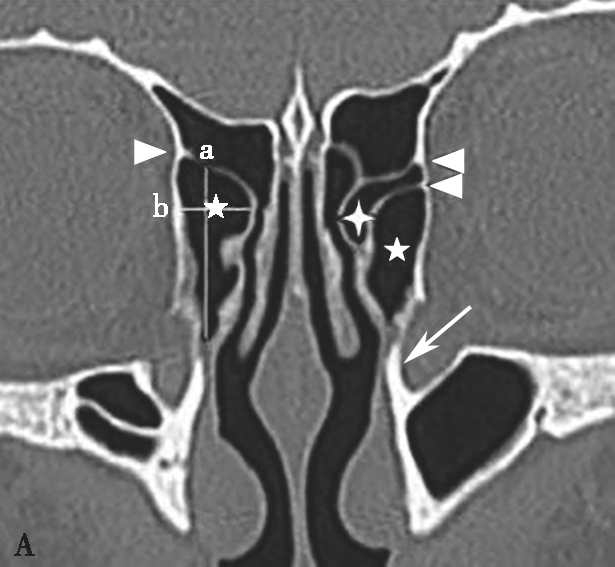

鼻丘气房位于筛漏斗的前上部,与泪骨、上颌骨、筛骨、额骨、鼻骨关系密切。是由筛漏斗直接发展而来。鼻丘气房通常位于额窦底的前部,构成额隐窝的前壁,大小不一,过大、过多可妨碍额窦引流,引起额窦炎。鼻丘气房和钩突眶内壁附着点之间的关系非常密切。当钩突与眶内壁没有附着点时,鼻丘气房不存在;当钩突与眶内壁仅有一个附着点时,鼻丘气房存在;当钩突与眶内壁有两个及以上附着点时,形成上下两个气房,在冠状面观察,偏下的气房称为鼻丘气房,偏上的气房称为额气房,两者内壁均由钩突构成(图1-3-1)。

图1-3-1 鼻丘气房及额气房CT解剖

A~C.鼻丘气房(五角星),额气房(星),钩突(白箭),筛骨纸板(箭头)